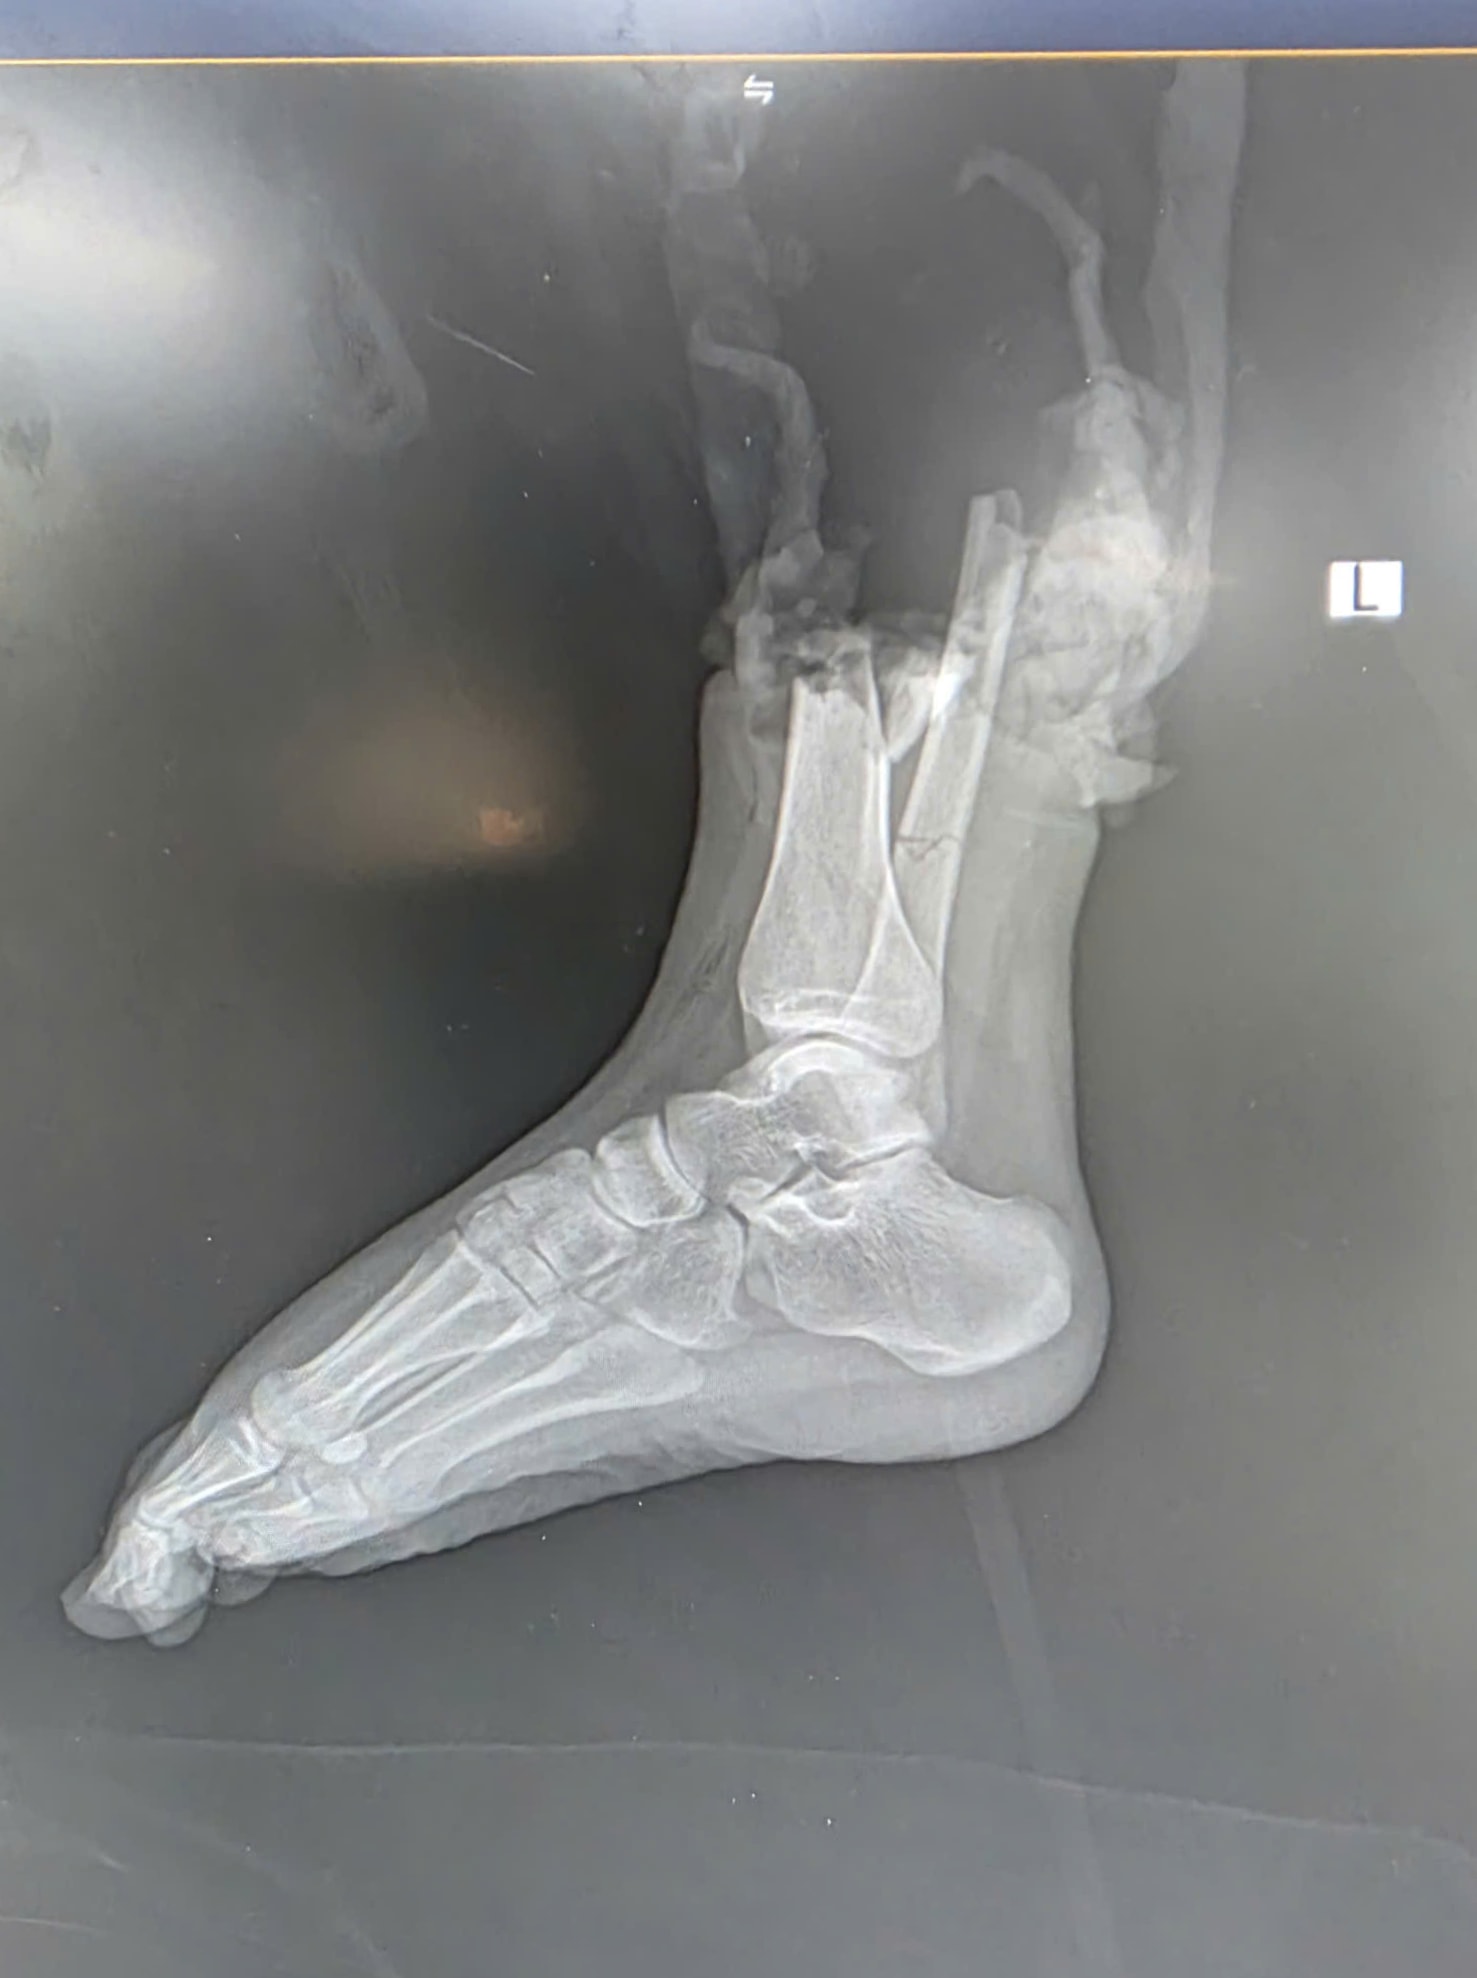

Hình ảnh tổn thương trên CT. Ảnh: BVCC

Sau cú va chạm mạnh giữa mô tô phân khối lớn và xe máy, nữ sinh Đ.P. (19 tuổi, quê Bắc Ninh) người điều khiển xe máy bị đứt lìa 1/3 dưới cẳng chân phải, kèm dập nát phần mềm.

Ca mổ kéo dài hơn 6 giờ, bao gồm các kỹ thuật cắt lọc, xử lý tổn thương, nối mạch máu, thần kinh, gân cơ và xương. Nhờ sự phối hợp nhịp nhàng giữa các ê-kíp phẫu thuật, phần chi thể đứt rời đã được trồng nối thành công.